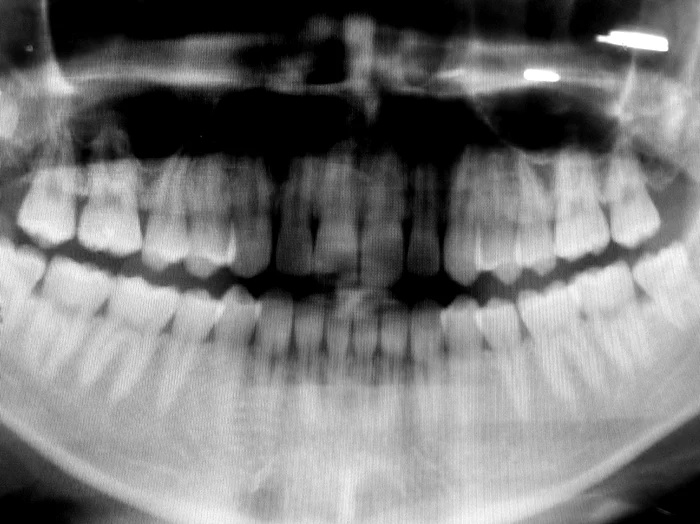

În ceea ce priveşte igiena orală, România stă jalnic. Statisticele europene ne situează pe primele locuri în ceea ce priveşte lipsa unei educaţii igienice orale şi suntem ţara unde unii dintre locuitori nu au văzut o pastă de dinţi în viaţa lor.

Aproximativ 20% din populaţia României nu s-a spălat niciodată măcar o dată pe dinţi, iar în ceea ce priveşte frecvenţa cu care conaţionalii noştri îşi schimbă periuţa de dinţi, suntem campioni. O dată la doi ani. De ce să ne luăm după nemţi, ei dau bani o dată la trei luni pe o periuţă nouă! Pe pastă de dinţi cheltuim cam jumătate din suma pe care o cheltuie cehii sau polonezii. Cei de la Vice au stat de vorbă cu medici dentişti ce-şi desfăşoara activitatea în România, oameni care se confruntă zi de zi cu cazuri ciudate și care sunt la curent cu toate metehnele românilor în privința igienei orale.